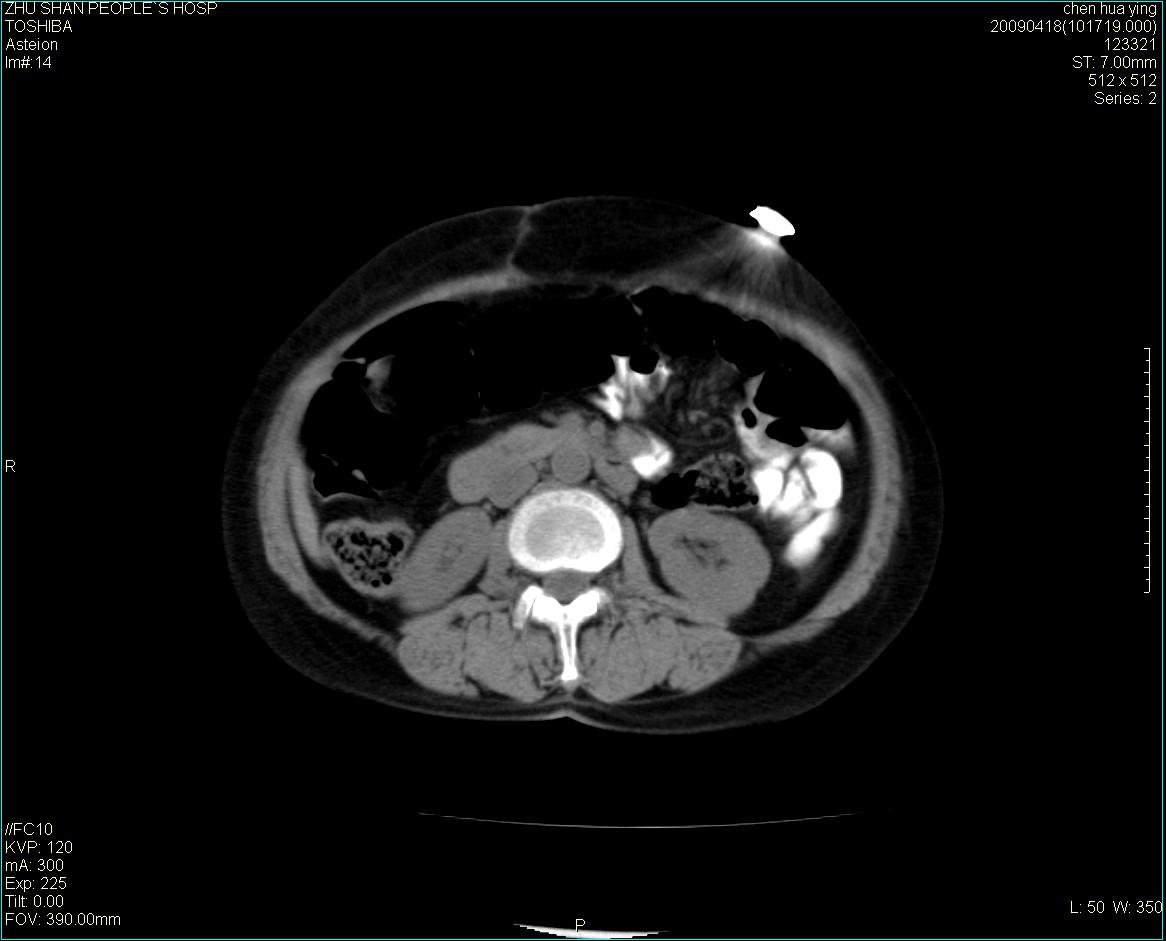

女性病人 65岁 腹部包块半年余结肠造影未见异常.

病灶略呈圆形有分叶状,上部层面呈实性,右侧见圆形低密度区,灶内见团块状钙化,病灶下方与肠管分境不清,考虑间质瘤可能性大,建议肠道准备后增强